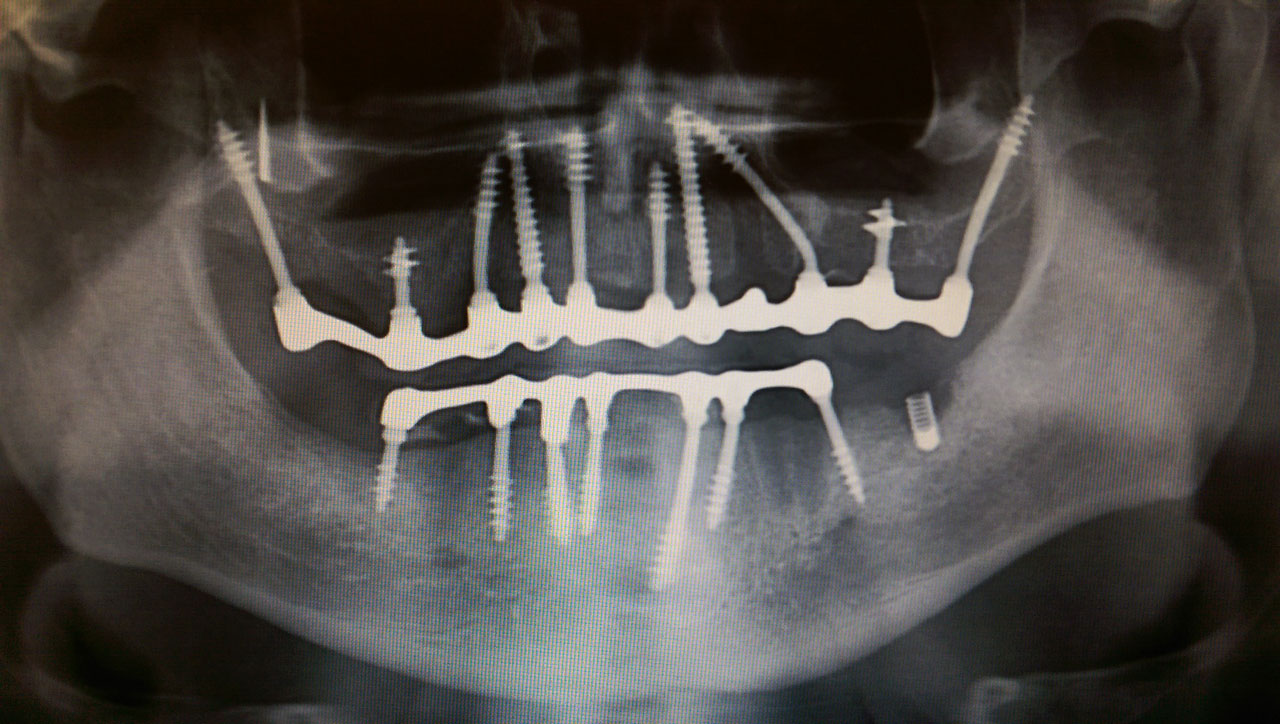

Teljes szájüregi rehabilitáció két lépésben

Ismét egy teljes szájüregi rehabilitáció két lépésben. Először az alsó fogak lettek kihúzva és azonnal implantálva, híddal ellátva, majd később a felső. IHDE svájci azonnal terhelhető implantátumok és cirkónium hidak. Dr. Kelemen Péter és a Symbion Fogtechnika közös munkája.